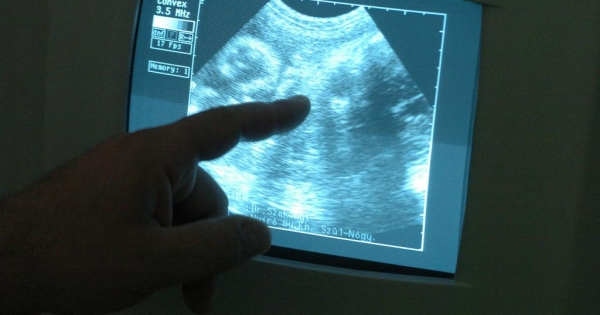

Inszemináció, lombikprogram – az eljárásokat igénybe vevő párok száma rohamosan nő. Bár a munkajogi szabályok védik az emberi reprodukciós eljárásban részt vevő női munkavállalót, a helyzet így sem egyszerű. Beavassuk-e a munkáltatót vagy sem? Mettől meddig tart egy eljárás? Mikor mondhatjuk, hogy befejeződött? Meddig nem szüntetheti meg a munkáltató felmondással a munkaviszonyt? Az újabb kezelés tartamára is jár védelem? Tudja meg cikkünkből!